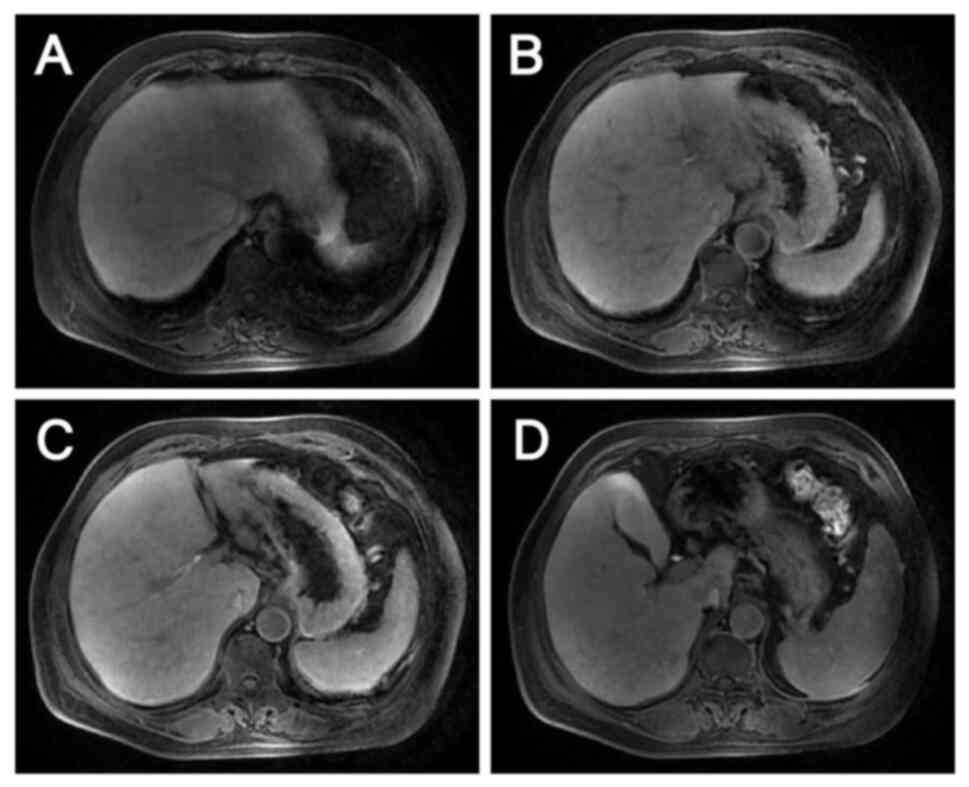

Metastatic liver lesions after 3

cycles of anti-HER2 therapy combined with chemotherapy as evaluated

by magnetic resonance imaging on January 25, 2024. (A-C) Metastases

in the S2, S3 and S4 segments of the liver are clearly reduced in

size compared with those on October 20, 2023. (D) The two lymph

nodes anterior and posterior to the portal vein are also less

enlarged.

Figure 8.

Metastatic liver lesions after 3 cycles of anti-HER2 therapy combined with chemotherapy as evaluated by magnetic resonance imaging on January 25, 2024. (A-C) Metastases in the S2, S3 and S4 segments of the liver are clearly reduced in size compared with those on October 20, 2023. (D) The two lymph nodes anterior and posterior to the portal vein are also less enlarged.